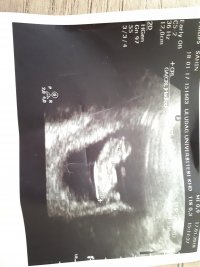

Hadi darısı bana insallah hayırlı olsunbenim nub teorisi doğru çıktı bebeğim kız 🙂

Birde şu görüntü var bunda peki bellimi ama burada 11 haftalikMerhaba canım bebeğinin pozisyonundan dolayı nub çıkıntısı görünmüyorki

Teşekkür ederim🙂Zaten şöyle söylim bu haftalarda yanılma payı çok yüksek bebeğin cinsiyetini yirminci haftalara yakın net olarak öğrenebilirsiniz . Allah hayırlısını versin inş.